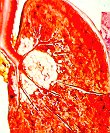

เป็นโรคปอดอักเสบจากการหายใจนำฝุ่นทราย (ซิลิก้า หรือซิลิกอนไดออกไซด์) เข้าไปสะสมในปอดจนเกิดการอักเสบหรือมีพังผืดขึ้นในปอด ซึ่งมักใช้เวลาไม่น้อยกว่า 3-5 ปี บางคนแม้หลังจากเลิกเกี่ยวข้องกับฝุ่นซิลิก้ามาหลายปีแล้วก็อาจมีอาการป่วยขึ้นได้

โรคนี้เกิดได้ทั้งแบบเฉียบพลันภายใน 5 ปี หรือแบบเรื้อรังค่อยเป็นค่อยไป 20-40 ปี มักเป็นวัณโรคปอดได้ง่าย มีอาการรุนแรงและรักษาหายยากกว่าคนทั่วไป ตรวจสมรรถภาพ ปอดมีความจุปอดลดลง ภาพถ่ายรังสีปอดผิดปกติพบจุดทึบเล็กๆ กระจายอยู่ทั่วไป